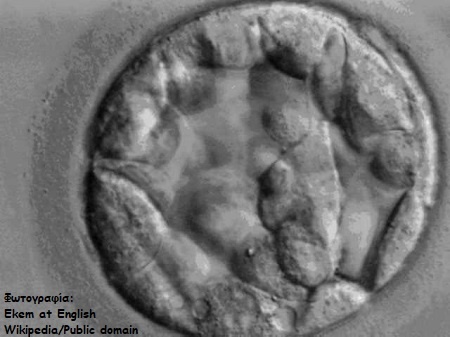

Στην παρακάτω φωτογραφία μπορούμε να δούμε ένα έμβρυο 3 ημερών, το οποίο αποτελείται από 8 έως 10 όμοια μεταξύ τους κύτταρα.

Πλέον όμως μπορούμε να καλλιεργήσουμε με επιτυχία έμβρυα στο εργαστήριο για 5 ημέρες. Το στάδιο αυτό της ανάπτυξης του εμβρύου ονομάζεται βλαστοκύστη (βλ. φωτογραφία).

Το έμβρυο στο στάδιο αυτό αποτελείται από 250 περίπου κύτταρα, τα οποία δεν είναι πλέον όμοια μεταξύ τους, αφού, όπως μπορούμε να διακρίνουμε και στην παρακάτω σχηματική απεικόνιση χωρίζονται σε δύο βασικές ομάδες: την εμβρυοβλάστη, εκ της οποία θα προκύψει αυτό καθαυτό το έμβρυο και κατ’ επέκτασιν το μωρό και την τροφοβλάστη, εκ της οποίας θα προκύψει ο πλακούντας.